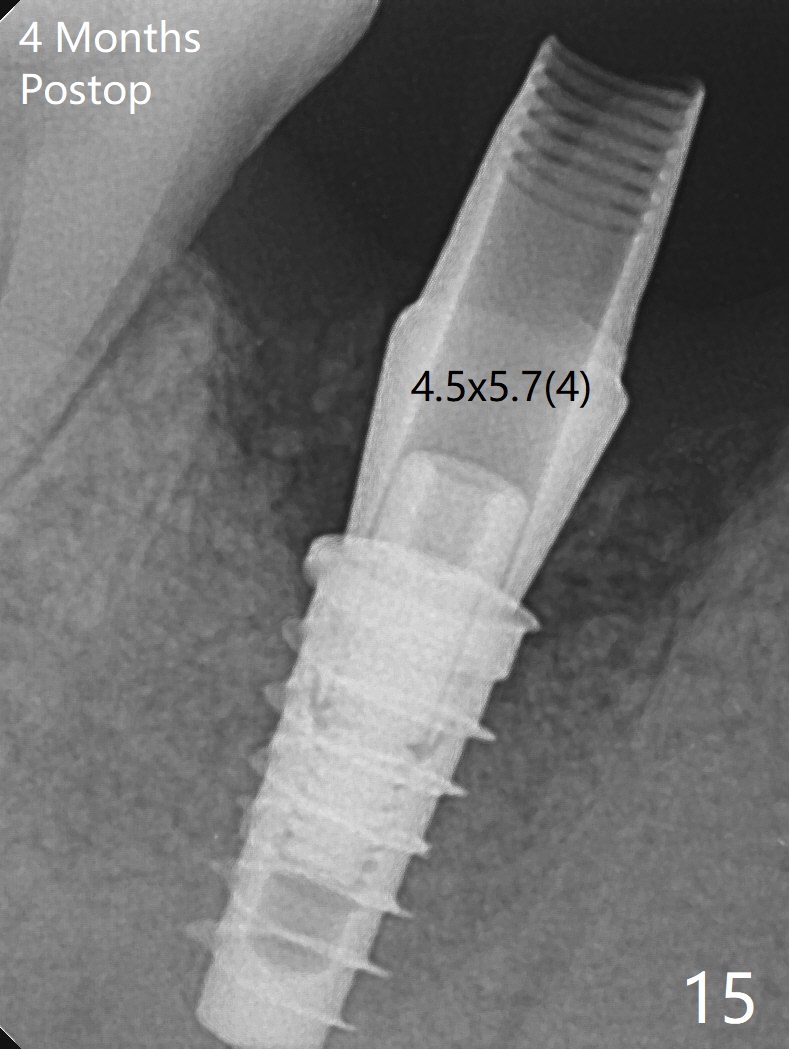

As planned, the crown of the tooth #30 with lingual (Fig.1 L) caries is removed and flattened with surgical handpiece so that the guide is able to be seated without interference. The osteotomy by 10.5 mm offset bone trimmer is lingual (Fig.2 white circle; due to in part the lingual caries and in part design error); in order to let the osteotomy to bounce back buccal, the part of the buccal roots are removed by surgical bur (arrows). The initial osteotomy by 2.2 mm drill is in the middle of the septum (Fig.3). After the last drill (3.5x11.5), the remaining roots are easily removed with proximators; a 4x11 mm dummy implant is placed with low stability and supracrestal lingual (Fig.4). Therefore a 4.5x9 mm final implant is placed with low torque. Following 4x11.5 mm drill, the torque increases to 20 Ncm. With insertion of healing screw, sticky bone (Fig.4 *: .5-1 mm cortical/cancellous allograft) is heavily packed around the implant (arrow), which apparently allows removal of the healing screw and placement of a 6x5.7(3) mm pair abutment without loosening the underlying implant. More bone graft is placed (Fig.6), followed by 2 pieces of PRF membranes. Although the implant is slightly buccally placed (Fig.7, due to over-removal of the buccal root, Fig.2 arrows), it is placed in the septum (Fig.8 S). To further compensate for the low implant stability, setting acrylic is applied in the edentulous area, particularly into the undercuts of the neighboring teeth (Fig.9 *) and around the abutment. The lingual margin of the acrylic dressing is extended (Fig.10 arrow) to cover the soft tissue defect associated with the lingual caries. As compared to the design (4x10 mm, Fig.11), the implant (4.5x9 mm, Fig.12) is placed buccal and ~ 2 mm deeper, reducing the chance of periimplantitis. The acrylic dressing is in place, but has mobility. The gingiva is healthy 2 weeks postop. The dressing is removed 1 month postop; the socket heals around the abutment buccal (Fig.13) and lingual (Fig.14). In spite of the immediate provisional, the abutment margin is substantially subgingival mesial 4 months postop, extremely difficult to take impression. A smaller diameter and longer cuff abutment is placed (Fig.15). The lingual gingiva heals normal 5 months postop, immediately before cementation (Fig.16).